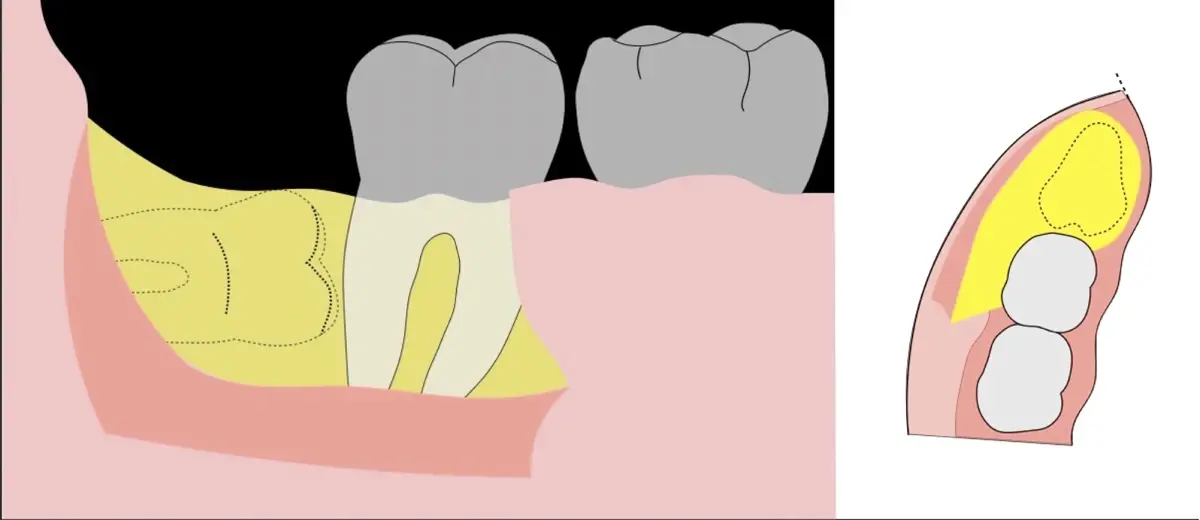

El procedimiento puede variar en su complejidad dependiendo de su ubicación, profundidad, angulación, y la densidad ósea circundante.2 Uno de los pasos más críticos y cruciales en la extracción es la osteotomía previa y concomitante al acceso quirúrgico del diente, para lo cual se utilizan diversos instrumentos como cinceles y martillos, instrumental rotatorio o de corte por ultrasonido.3

En contraste, el instrumento piezoeléctrico utiliza un corte micrométrico que retira un área de superficie mínima de hueso, y reduce el riesgo de termonecrosis marginal en comparación con las fresas rotatorias convencionales.9 Los micromovimientos mejoran la precisión en el corte y el control táctil, y eliminan las macrovibraciones que se producen con los instrumentos rotatorios.10 Su frecuencia de oscilación es la amplitud de 60-200 μm horizontalmente y de 20-60 μm en sentido vertical, lo que es muy inferior en comparación con las micro sierras oscilantes; por lo tanto, proporciona cortes de osteotomía precisos y seguros. Adicionalmente, posee vibraciones ultrasónicas que descomponen el líquido de irrigación en partículas muy pequeñas (fenómeno de cavitación, que produce un efecto hemostático y así reduce la pérdida de sangre), lo que proporciona una visión clara y sin obstáculos del campo quirúrgico11,12.